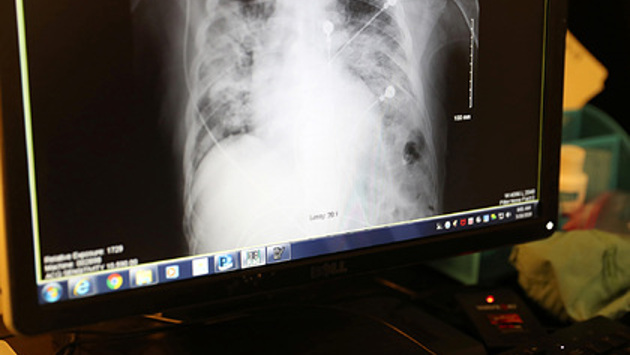

Главный патологоанатом клинической больницы Иркутска Людмила Гришина описала состояние легких умерших пациентов с коронавирусом после вскрытия. По словам медика, орган значительно отекает и весит в несколько раз больше положенного. Ее слова приводятся на сайте «Вести.ru».

Патологоанатом отметила, что смерть пациентов с коронавирусом зачастую наступает в результате тромбоэмболии — закупорки легочной артерии.

«Появляется массивный отек. Нарушается микроциркуляция, что приводит к кровоизлиянию в просвет альвеол. Сегодня было вскрытие — абсолютно соматически здоровый человек. Печень, сердце — все в порядке. Но каждое легкое весило по 1,5 килограмма»,

— добавила Гришина.